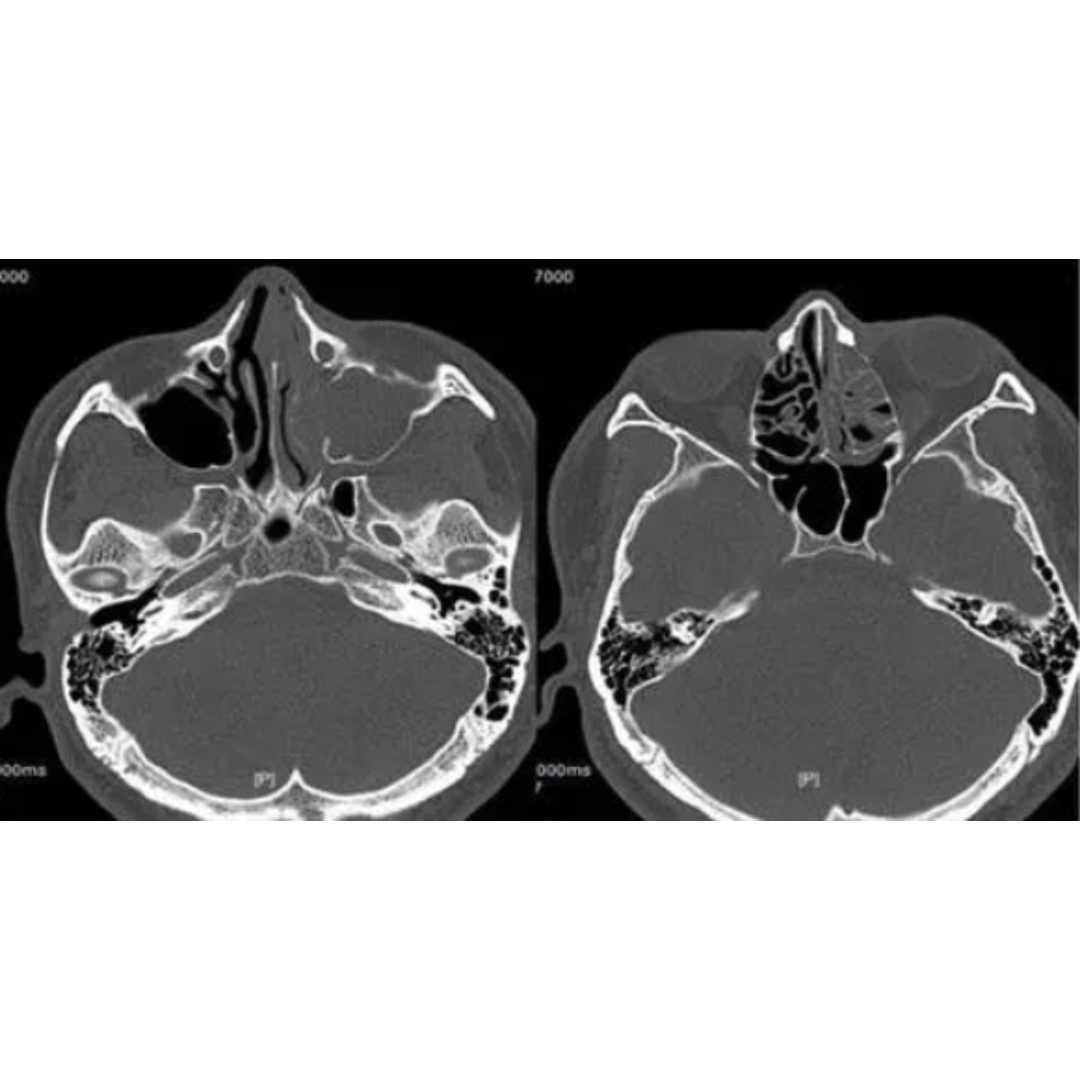

头颅ct!蝶窦层!

图片尺寸1280x1706